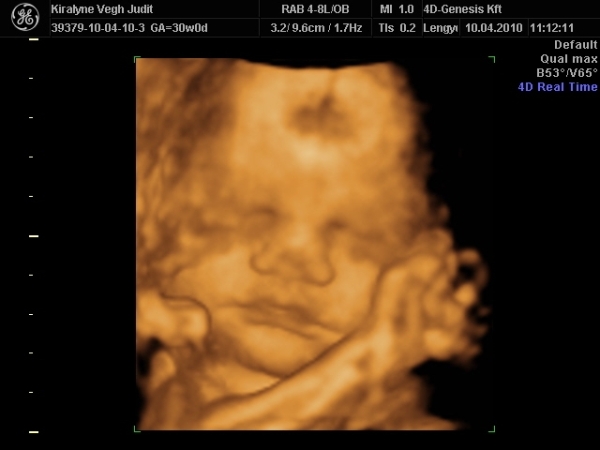

4D-re holnap megyünk 11-re, utána meg tervezünk egy kis csavargást. :lol: :lol: :lol:

Ma jól elfáradtam. Voltunk 4D-n, a várban és a Csodák palotájában. Rengeteget sétáltunk, nem érzem a lábamat.

A lényeg, hogy Izi baba nagyon jól van,

Babócám fejjel lefele, idézem: "méhlepény olyan távol van a méhszájtól, mint Makó Jeruzsálemtől." :oops: :oops: :oops:

Szóval nem értem a szerdai uh-ot. :oops: :oops:

"0" fokban érett a lepény, 1741g kis csöppségem, combcsont mérete alapján már 32 hetesnek felel meg. Amúgy minden mérete alapján 1 héttel idősebb. Magzatvíz átlagos. És tiszta apja. :lol: :lol: :lol: :lol:

És a képek.